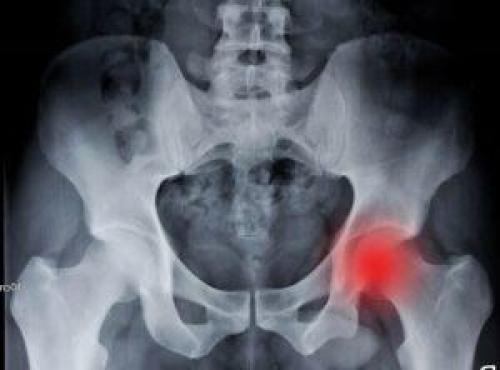

Коксартроз тазобедренного сустава 3 степени характеризуется запущенным протеканием заболевания: у больного наблюдается обширное поражение бедренной и тазовых костей. Человек не может нормально передвигаться и ходить без дополнительной опоры.

Коксартроз правого тазобедренного сустава 3-й степени (на снимке — слева).

Коксартроз 3 степени тазобедренного сустава может развиться, если больной в течение длительного времени не будет предпринимать никаких терапевтических действий по отношению к купированию начальных стадий заболевания. Существенно повышают риск запускания коксартроза несвоевременное обращение к врачу и бесконтрольная практика самолечения.